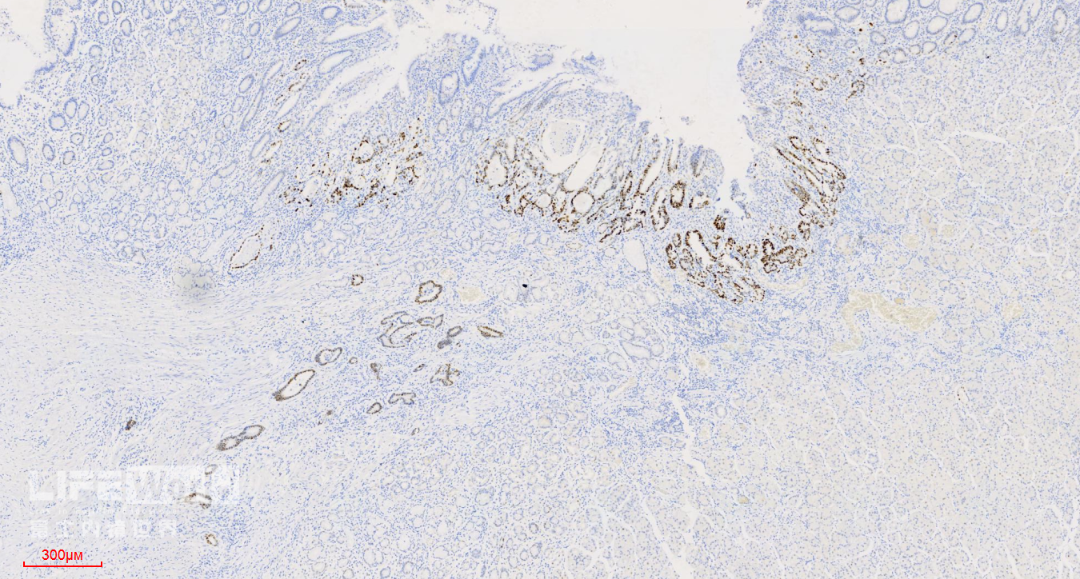

CK-pan染色显示肿瘤细胞为上皮细胞,呈不规则腺管状排列,提示为中分化腺癌。

SMA染色:粘膜肌层完整,肿瘤细胞侵及粘膜肌层,但未突破。